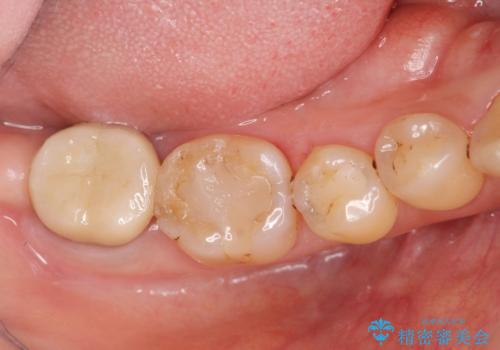

歯周病に対する全体治療

- 近医で「重度の歯周病です、入れ歯にする必要がある。」、と言われ入れ歯以外の方法がないか相談にみえられました。

再生治療、歯周外科を行うことで歯周病治療を行い、残すことのできる歯の歯周環境を整える。

残すことのできない歯は抜去したのち骨造成を含めたインプラント治療を行い、しっかりとした咬合関係を確立していきます。

治療期間はかかりましたが、しっかりと歯周病治療・インプラント治療を行ったおかげで歯周病の状態は非常に良くなり、安定した咬合関係を確立することができました。